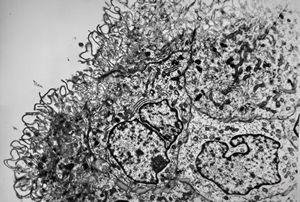

M,3y. | globoid leukodystrophy of Krabbe - n.suralis